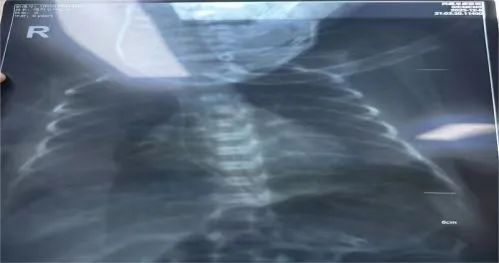

接到护理会诊通知后,静疗团队 (IVTEAM) 高度重视,认真评估患儿情况,来到科室映入眼帘的是温箱里四肢仅有拇指粗细,血管更是细如发丝的早产宝宝,了解到普通留置针穿刺实属不易,但置入 PICC 更是难上加难,对于我们静疗团队来说是无疑是一个巨大的挑战。在 ICU 任周行护士长的指导下,静疗学组组长韩晓倩、邓倩雯准备好物品,代金丽护士长小心翼翼地为宝宝摆好体位,大家一起做好基本生命支持及保暖工作,充分评估血管情况后,组长韩晓倩最终选择经右上肢贵要静脉进针,凭借过硬的穿刺技术,穿刺时一针见血,随后送管、撤导丝、固定一气呵成,经 X 线定位确定 PICC 导管尖端位置良好,成功了,大家终于松了一口气!